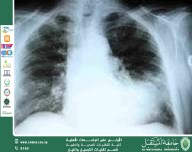

مقالة علمية للست شهد نورس عباس بعنوان وجود السوائل على الرئة (Pulmonary Edema)

وجود السوائل على الرئة (Pulmonary Edema) المقدمة يُعد وجود السوائل على الرئة، المعروف علميًا باسم الوذمة الرئوية (Pulmonary Edema)، من الحالات الطبية الخطيرة التي تنتج عن تراكم السوائل داخل الحويصلات الهوائية والأنسجة الرئوية، مما يعيق عملية تبادل الغازات ويؤدي إلى صعوبة في التنفس. وتُعد هذه الحالة من الطوارئ الطبية التي تتطلب تشخيصًا وعلاجًا سريعًا لتفادي المضاعفات الخطيرة. التعريف العلمي الوذمة الرئوية هي حالة مرضية يحدث فيها تسرب السوائل من الشعيرات الدموية إلى الحويصلات الهوائية في الرئتين، نتيجة اضطراب في الضغط الهيدروستاتيكي أو النفاذية الوعائية، مما يؤدي إلى نقص الأكسجين في الدم. أسباب وجود السوائل على الرئة تنقسم أسباب الوذمة الرئوية إلى نوعين رئيسيين: الوذمة الرئوية القلبية (Cardiogenic Pulmonary Edema): تحدث نتيجة فشل القلب الأيسر في ضخ الدم بكفاءة، مما يؤدي إلى ارتفاع الضغط في الأوعية الدموية الرئوية وتسرب السوائل إلى الرئة. ومن أهم أسبابها: فشل القلب الاحتقاني احتشاء عضلة القلب اضطرابات صمامات القلب الوذمة الرئوية غير القلبية (Non-cardiogenic Pulmonary Edema): تحدث دون وجود خلل مباشر في القلب، ومن أسبابها: الالتهابات الرئوية الشديدة متلازمة الضائقة التنفسية الحادة (Acute Respiratory Distress Syndrome – ARDS) استنشاق المواد السامة أو الدخان الإصابات الرضحية والصدمة الأعراض السريرية تظهر على المصاب عدة أعراض تختلف حسب شدة الحالة، ومنها: ضيق شديد في التنفس السعال المصحوب برغوة بيضاء أو وردية اللون تسارع ضربات القلب الشعور بالاختناق خاصة عند الاستلقاء ازرقاق الشفاه والأطراف في الحالات المتقدمة التشخيص يعتمد تشخيص الوذمة الرئوية على مجموعة من الفحوصات السريرية والمخبرية، من أهمها: الفحص السريري وسماع أصوات الرئة تصوير الصدر بالأشعة السينية (Chest X-ray) تحليل غازات الدم الشرياني تخطيط صدى القلب (Echocardiography) لتحديد السبب القلبي العلاج يركز علاج السوائل على الرئة على إزالة السبب الأساسي وتحسين وظيفة التنفس، ويشمل: إعطاء الأكسجين لتحسين نسبة التشبع مدرات البول (Diuretics) لتقليل تراكم السوائل أدوية دعم القلب في الحالات القلبية التهوية الاصطناعية في الحالات الشديدة المضاعفات في حال عدم العلاج المناسب، قد تؤدي الوذمة الرئوية إلى: فشل تنفسي حاد نقص حاد في الأكسجين توقف القلب في الحالات الحرجة الخاتمة يُعد وجود السوائل على الرئة من الحالات الطبية الخطيرة التي تستوجب تدخلاً عاجلاً، ويعتمد نجاح العلاج على سرعة التشخيص ومعالجة السبب الأساسي. كما أن التوعية بالأعراض والعوامل المؤدية للحالة تساهم في تقليل معدل المضاعفات وتحسين فرص الشفاء. جامعة المستقبل الجامعة الاولى في العراق